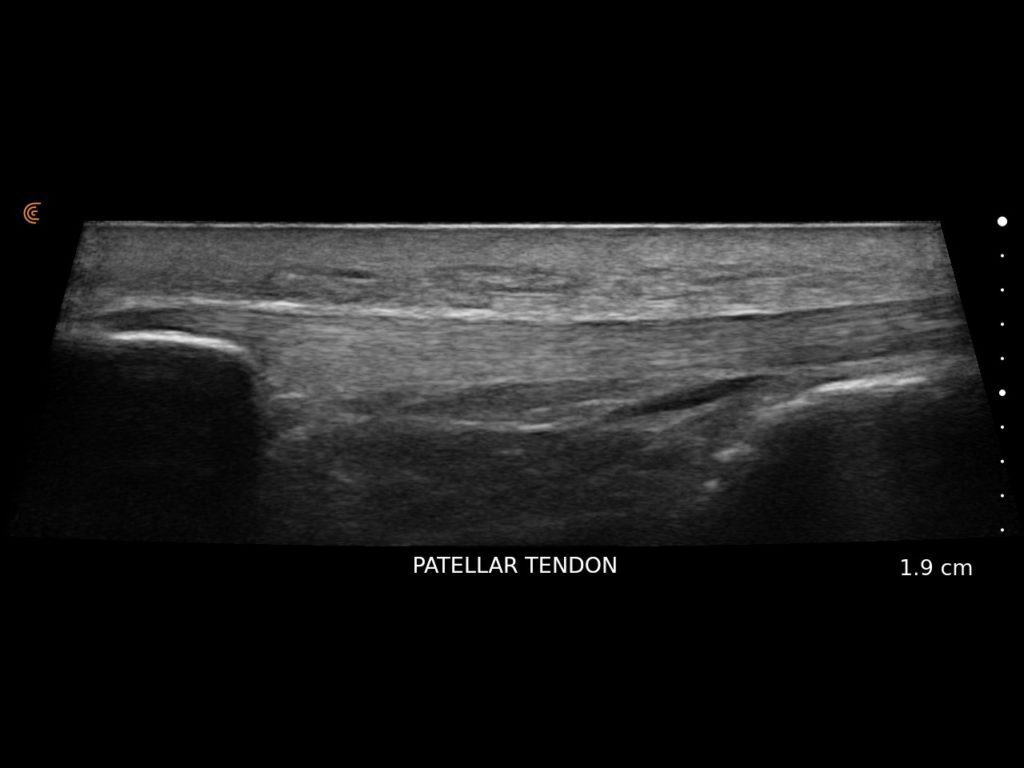

Clarius HD3 is the ideal wireless ultrasound scanner for musculoskeletal (MSK) imaging and procedural guidance. Make a confident diagnosis with high-resolution imaging of muscles, joints, ligaments, tendons, and cartilage both at rest and in motion.

What I like about Clarius is that it is an excellent ultrasound that allows me to have versatility, quality and precision.